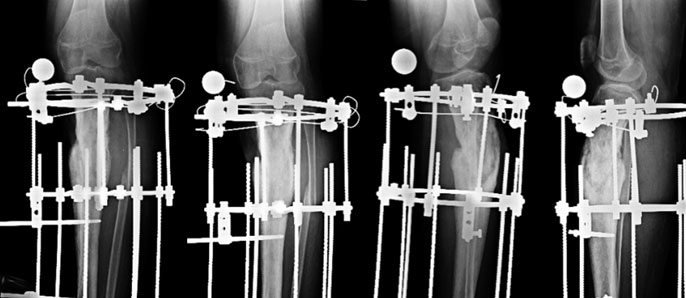

| At Presentation |

| 15 year old boy, presented with mobile nonunion of upper 1/3rd of tibia of 7 months duration. He had developed a pathological fracture secondary to osteomyelitis which was secondary to a previous surgery for hematoma evacuation. There was no sign of an active infection on presentation. |

2 days after surgery

During the surgery an Ilizarov ring fixator was applied. The fibula was cut (red arrow) to allow compression at fracture site. Gradual compression was done and he was encouraged to bear full weight. |